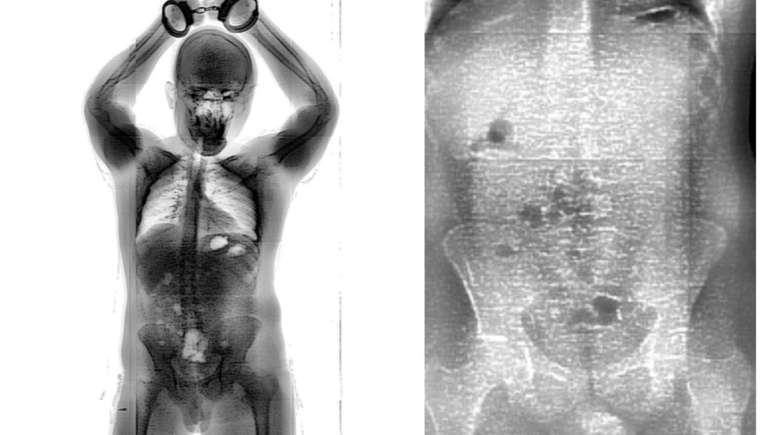

Preso foi flagrado pelo BodyScan com 18 “bolinhas” de maconha no intestino

Raio-x mostrou pacotes de maconha no intestino do homem

Foto: Divulgação/Seap

Um preso foi flagrado tentando entrar com maconha no Conjunto Penal de Brumado, no sudoeste da Bahia. O homem, que não teve a identidade revelada, engoliu 18 invólucros contendo porções da droga com a intenção de entrar com o material ilícito na unidade.

Segundo a Secretaria de Administração Penitenciária e Ressocialização (Seap), a tentativa de entrar com a droga no local foi frustrada por causa da BodyScan, scanner corporal que apontou alterações na região intestinal do homem. O caso aconteceu na sexta-feira, 15, mas foi revelado pela Seap na noite deste domingo, 17.